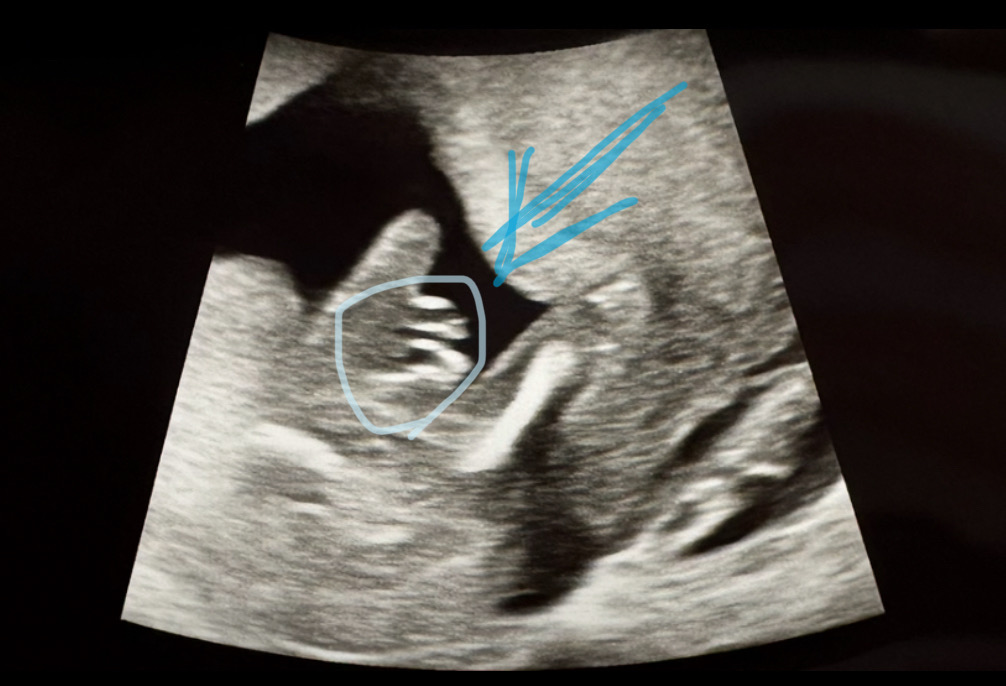

15주3일 성별확인하고 왔어요

춈파 갖다대자마자 저기를 가르키시며 뭐가 튀어나와있네요~ 하시더라구요 뭔가~ 임신 초기부터 계속 아들일것같다는 느낌이 들었는데 오늘 드디어 확인했네요 아들맘 입니다~~~💙